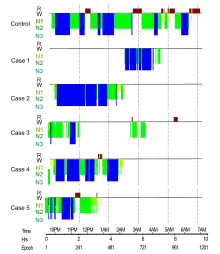

Clinically, FFI manifests with a disordered sleep-wake cycle, dysautonomia, motor disturbances, and neuropsychiatric disorders.

Other symptoms include profuse sweating, miosis (pinpoint pupils), sudden entrance into menopause or impotence, neck stiffness, and elevation of blood pressure and heart rate. The sporadic form of the disease often presents with double vision. Constipation is common as well. As the disease progresses, the person becomes stuck in a state of pre-sleep limbo, or hypnagogia, which is the state just before sleep in healthy individuals. During these stages, people commonly and repeatedly move their limbs as if they’re dreaming.[7]

The age of onset is variable, ranging from 13 to 60 years, with an average of 50.[8] The disease can be detected prior to onset by genetic testing.[9] Death usually occurs between 6–36 months from onset. The presentation of the disease varies considerably from person to person, even among people within the same family; in the sporadic form, for example, sleep problems are not commonly reported and early symptoms are ataxia, cognitive impairment, and double vision.[10]